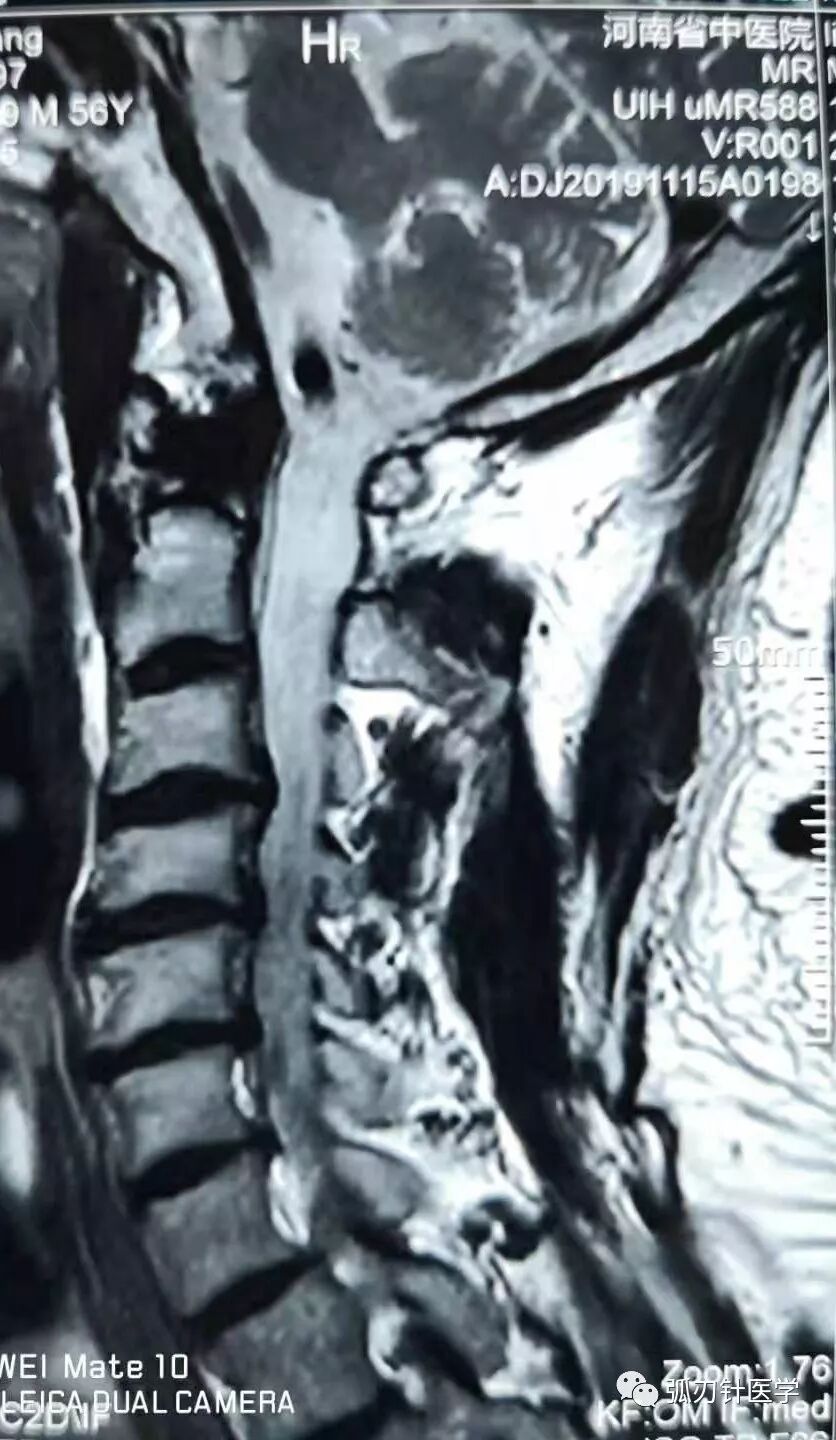

胳膊麻、脖子疼,一个中年男性患者典型的颈椎片和磁共振:骨质增生、项韧带钙化、椎间盘突出、椎间孔狭窄……